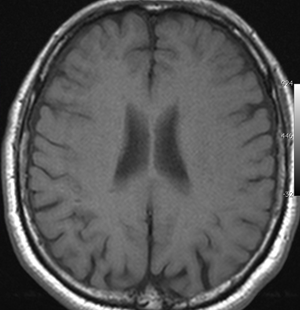

小さな多発性の海綿状血管腫は,T2*(ティーツースター)という左の画像では見えるのですが,右にあるような普通のT1強調画像というのでははっきりみえません。